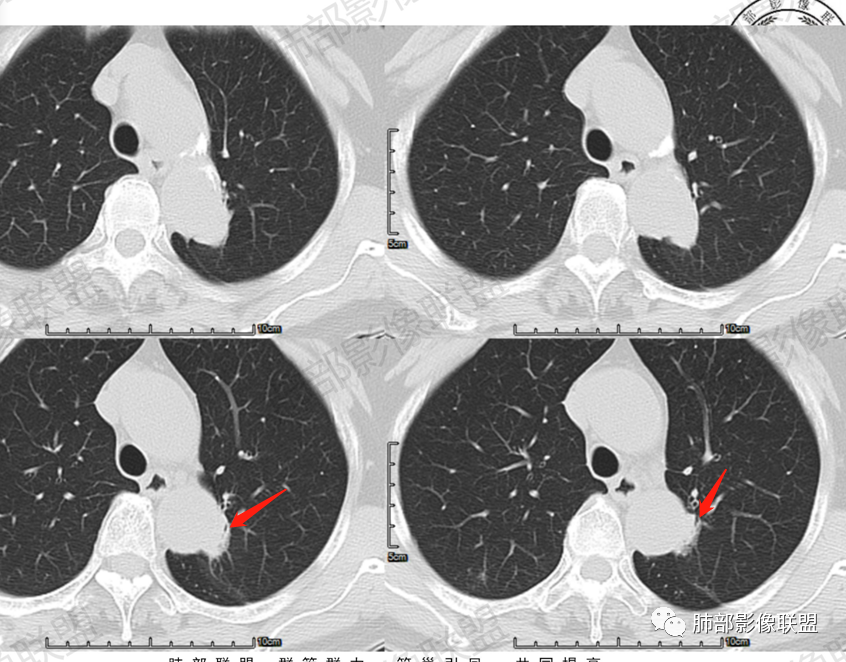

一、病例资料

2.轴位显示主动脉弓旁依势傍行弧形高密度影,隐约见尖后段支气管进入并截止。病灶边界较清楚,见血管结构及线性影与邻近肺组织相延伸。

3.病灶渐进性显著均匀强化!动脉期未见主动脉腔异常通道。